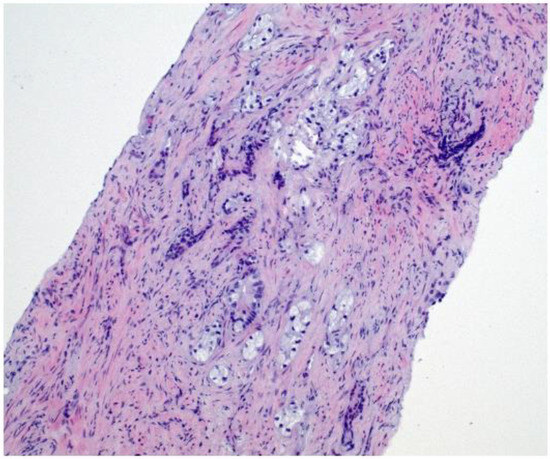

Given the persistent re-accumulation of pleural effusion and suspicious nodular pleural thickening, a diagnostic video-assisted thoracoscopic surgery (VATS) was performed. Approximately 900 mL of bloody fluid was drained, and multiple pleural nodules were biopsied. Histopathology revealed metastatic carcinoma. Immunohistochemical staining demonstrated positivity for androgen receptor (AR), alpha-methylacyl-CoA racemase (AMACR), and focal Prostein, alongside negativity for TTF1, CK20, WT1, D2-40, PAX8, GATA3, and CDX2, consistent with a primary prostatic origin [8]. Figure 4 Digital rectal examination (DRE) revealed a firm prostate gland with bilateral palpable nodules consistent with clinical stage T2c disease. Although the patient’s serum PSA was only 2.91 ng/mL, a subsequent prostate MRI revealed a PIRADS 5 lesion invading bilateral seminal vesicles Figure 5, Figure 6 and Figure 7, and a transrectal fusion biopsy confirmed ISUP grade group five disease (Gleason 4 + 5 = 9). Figure 8 A bone scan showed no skeletal metastases, and a contrast-enhanced CT of the abdomen found no evidence of abdominal metastatic disease (notable findings included multiple simple hepatic and renal cysts, and a homogeneous left adrenal adenoma). The patient was staged as cT3bN0M1 (pleural metastasis) and started on androgen deprivation therapy with bicalutamide plus leuprolide, followed shortly by abiraterone and low-dose corticosteroids. Three-month follow-up imaging demonstrated stable pleural disease and partial symptomatic relief in his respiratory complaints.

Figure 4. HE image showing pleural fibrous tissue infiltrated by clear cell adenocarcinoma (positive for panCK, AR and AMACR, negative for TTF1, not shown). Magnification: 20×.